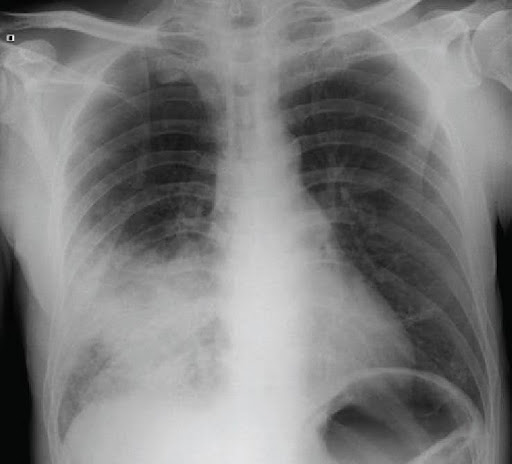

Chest X-ray: helps assess the presence, location and extent of lung inflammation.